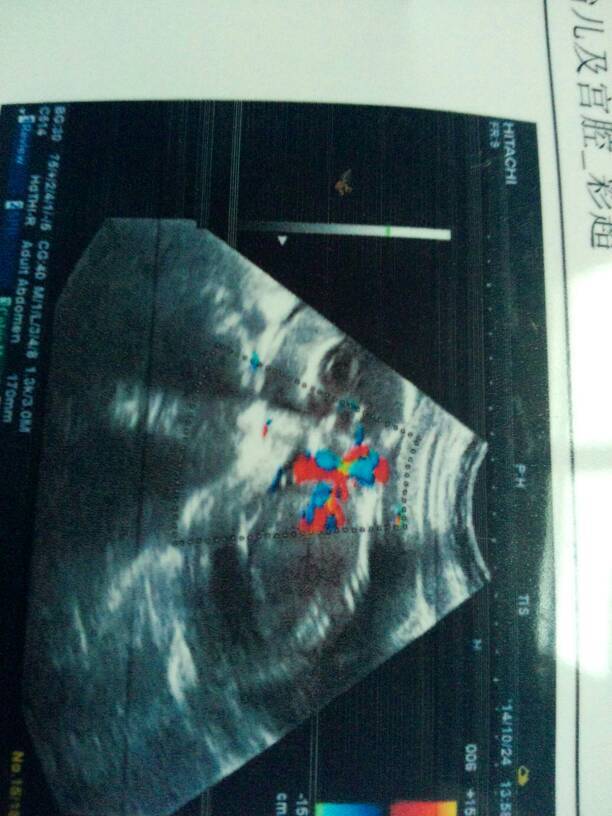

这张能看清楚是男孩还是女孩 这张能看清楚是男孩还是女孩 点击展开 倪宝贝 2014-10-24 17:16 为您推荐: 其他回答 你好,根据图片不能判断是男是女,只能15周以后通过B超动态观察胎儿性别。孕期保持良好情绪。孩子发育的就错不了。 张笑珠 2014-10-24 20:42 看不出来、 梓欣宝宝 2014-10-24 19:10 相关问题 没写男孩女孩啊!下一张能有结果吗? 晕今下午去做B超看看男孩,女孩医生说我肚子油太多看不清楚,现在四个月,等五六个月能看清楚吗